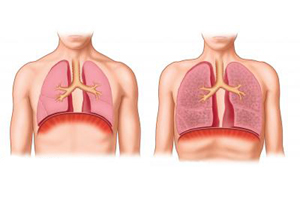

Итак, межнациональная команда специалистов под руководством профессора Мачьярини при помощи нанотехнологий построила этим летом своеобразный макет трахеи из синтетического материала. После этого у пациента были взяты стволовые клетки, которые в специально разработанном «биореакторе» были подсажены на каркас органа. В течение двух дней была достигнута необходимая для трансплантации кондиция искусственной трахеи. Благодаря тому, что использованные для регенерации органа клетки принадлежали самому больному, они не вызывают отторжения и принимаются организмом «за свои», а пациенту не нужно пить вредные иммунодепрессанты. Более того, мужчина находится на пути к полному выздоровлению и уже выписан из больницы.

Трансплантация тканей и органов, разработанных по подобной технологии регенеративной медицины, с использованием синтетического каркаса и стволовых клеток пациента открывает новые и весьма перспективные терапевтические возможности. Тысячи пациентов, которые страдают от рака или других разрушающих организм заболеваний, будут освобождены от необходимости ждать подходящего донора. Это существенный выигрыш, ведь ранняя хирургия даёт больше шансов на излечение. Особенно важен успех описываемой операции для детей, которым необходима трансплантация трахеи, ведь донорские трахеи для них – большая редкость.